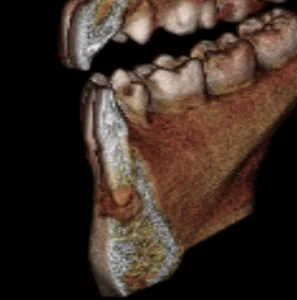

Second, I was able to utilize the dramatic effect of such a high resolution volume to educate the patient in a clear and compelling way. I was able to stress the importance of taking care of this situation.

Finally, and most importantly, I’m confident that my proposed treatment plan is optimal for the patient in that it maximizes effectiveness while minimizing invasiveness.